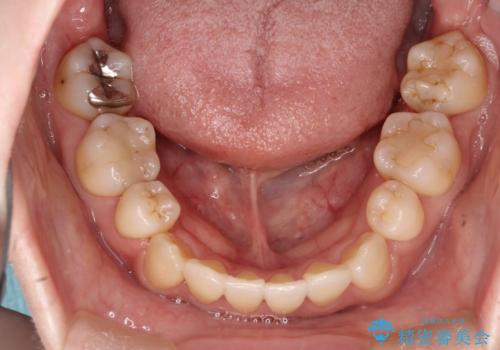

初診時の歯並びの状態としては、上下に強いガタガタがある状態であり、それが原因で口腔内の清掃状態も極めて悪い状況でした。

スペースの不足量が著しく、上下左右の抜歯を伴うワイヤー矯正にて治療を行いました。

抜歯によるスペースを利用し、強いがたつきの改善を行いました。